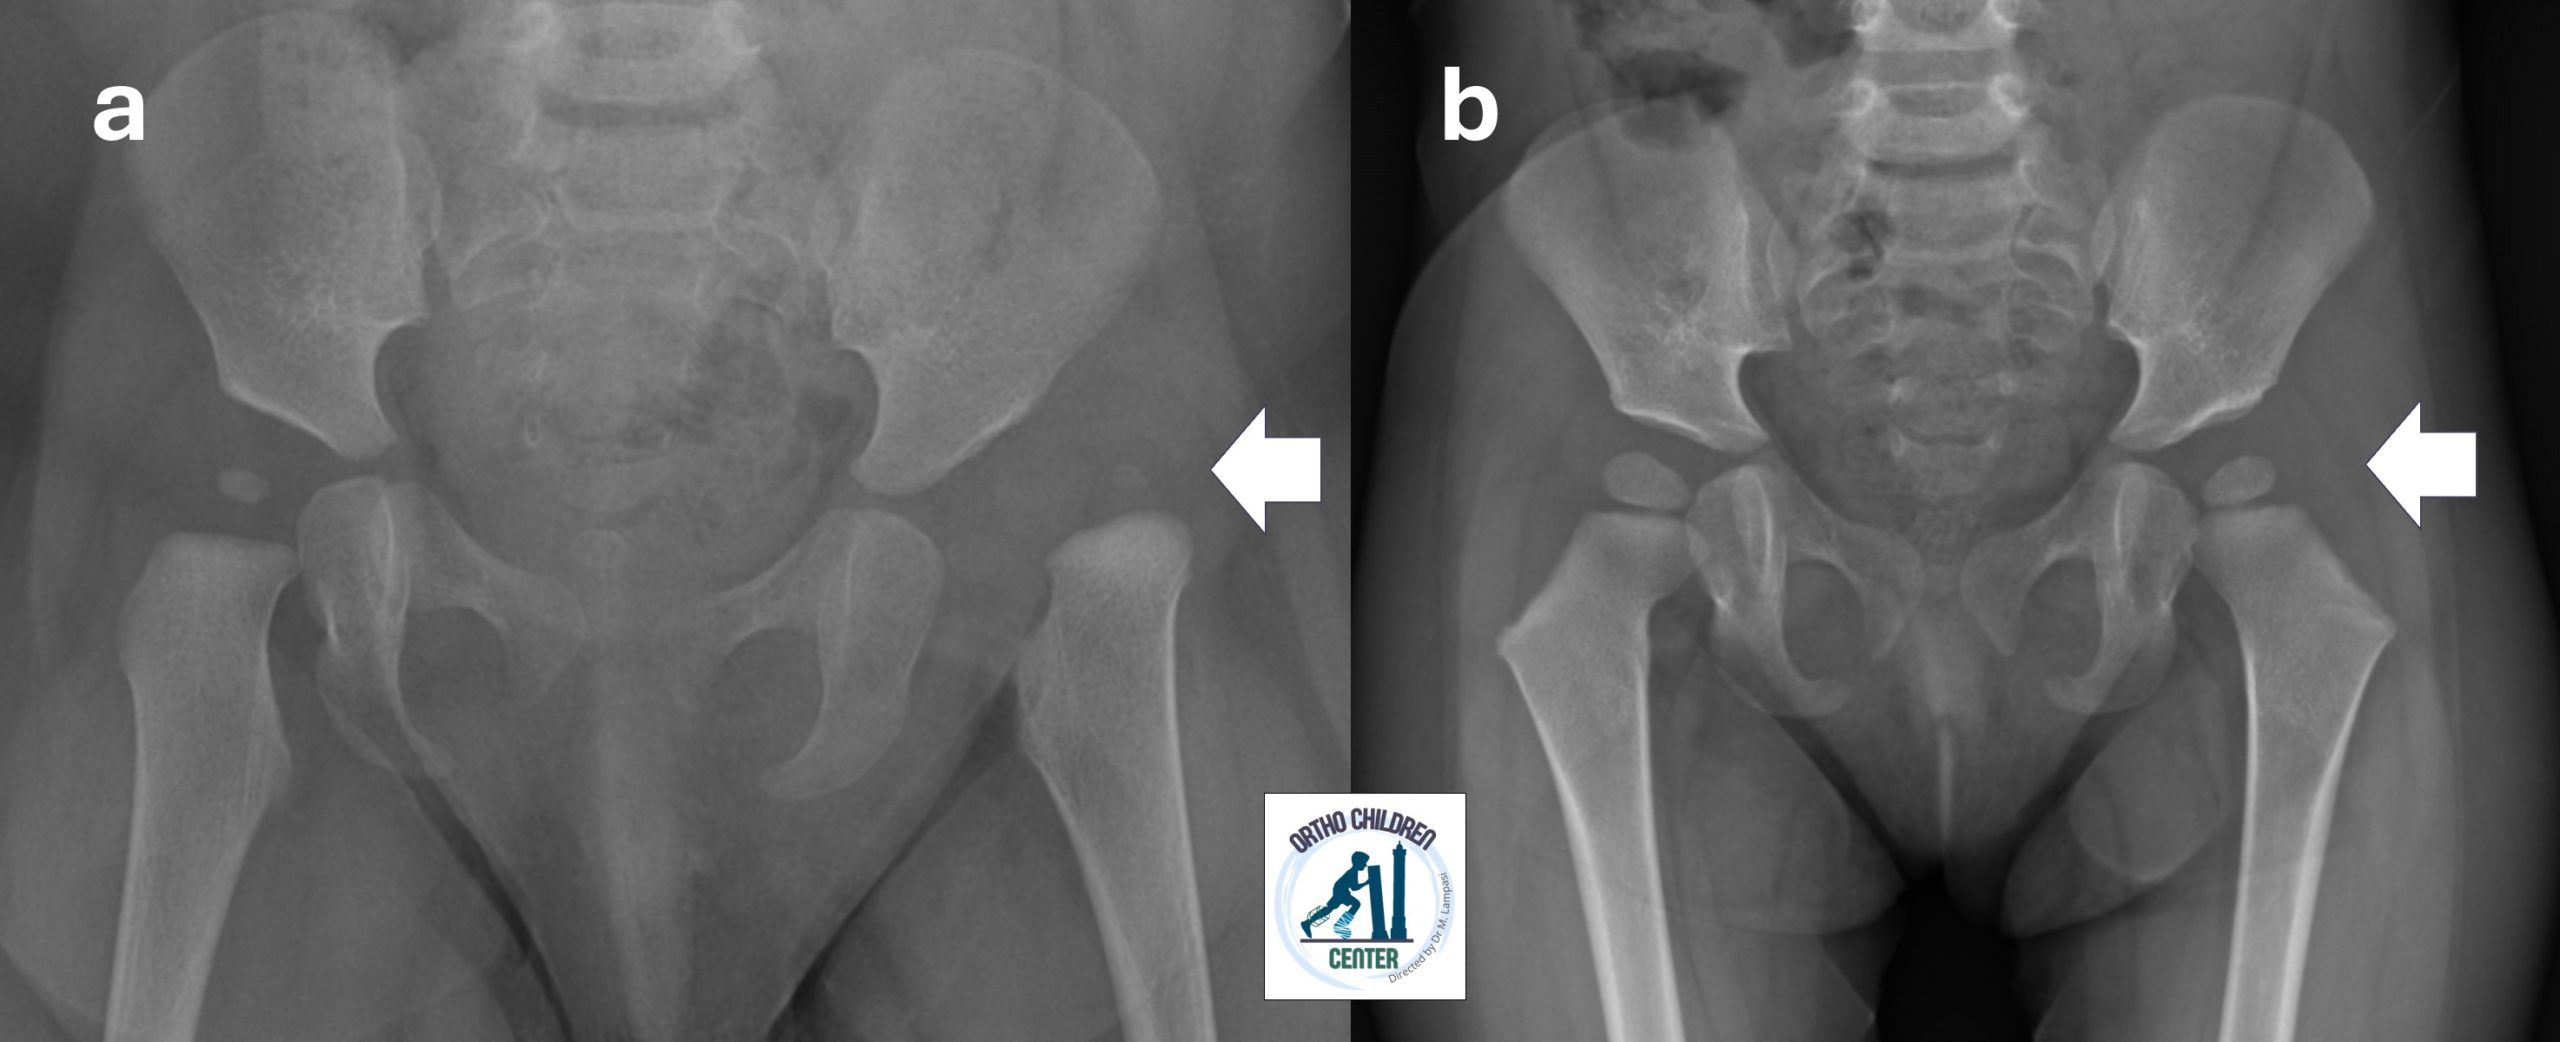

Bimba di 9 mesi con lussazione congenita dell’anca sinistra diagnosticata tardivamente, giunta alla nostra osservazione dal Regno Unito.

Nel nostro Centro una corretta valutazione clinica iniziale e l’utilizzo adeguato di ecografie, radiografie e ortesi hanno consentito di ottenere il risultato senza necessità di trazione, anestesia o gessi. Le radiografie a 18 mesi di distanza mostrano buona centrazione, senza segni di necrosi avascolare (AVN).

📌 9-month-old baby with hip dislocation (developmental dysplasia of the hip). In other reference centres, the following procedures were proposed: traction (2 weeks), cast (3 months), procedures under anaesthesia. In our Center the treatment was carried out without traction, without anesthesia, without cast.

Radiographs at 18 months show good centration, without signs of AVN.